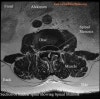

MRI : 요추 척추관협착증(Lumbar spinal stenosis)

- CT : MRI에 비해 골조직의 이상에 의한 협착증을 용이하게 진단

- MRI : 협착증 진단에 가장 우수한 검사